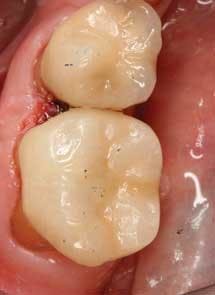

The restoration of teeth in a single visit can now be measured in minutes instead of hours, and does not involve performing large, direct restorations that may not be clinically indicated and where the limits of the restorative materials are pushed. Indirect restorations can now be milled chairside from a solid, homogenous block of porcelain to restore the tooth to optimum fit, function, and esthetics (Figure 2).